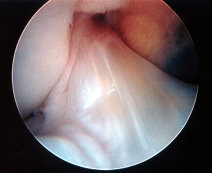

ACL Rupture

Exclude combined ACL+ Meniscal Detachment

• Whenever a meniscal avulsion is suspected